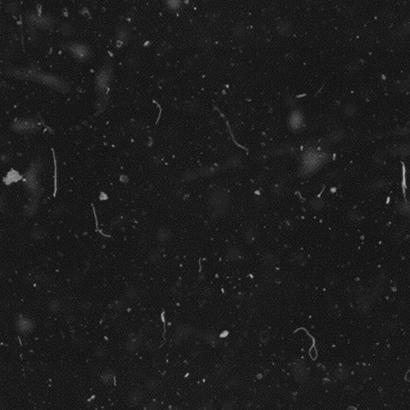

Irregular and Rippled SurfaceShows height variations that compromise image consistency and quality. |

Risk of Inefficient WorkflowsCan lead to suboptimal scans, reducing lab efficiency and requiring time-consuming rescans. |